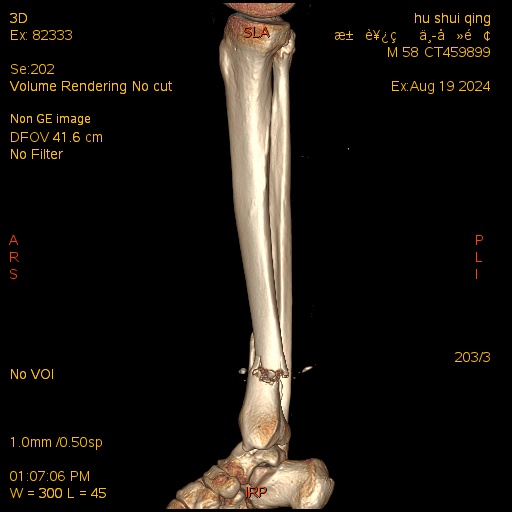

术前三维CT

患者胡某,男,58岁,因锐器切割致右下肢开放性损伤3小时入院。入院后诊断为:1.开放性胫骨下端骨折2.下肢神经的损伤3.下肢血管的损伤4.跟腱断裂5.下肢肌腱损伤。患者入院后立即急诊行右下肢清创术+胫神经缝合术+胫动脉缝合术+跟腱缝合术+胫骨远端克氏针临时固定术。术后3周后患者开放伤口处皮肤顺利愈合并拆线,拟进行二次手术对胫骨远端骨折进行终极固定。骨伤医院院长梁卫东及创伤骨科杨阳主任医师团队对该患者开展详细的病情讨论,并制定详细周密的手术计划及术后康复计划,同时在患者及其家属知情同意后,实施胫骨远端骨折逆行胫骨髓内钉内固定术,并取得成功。